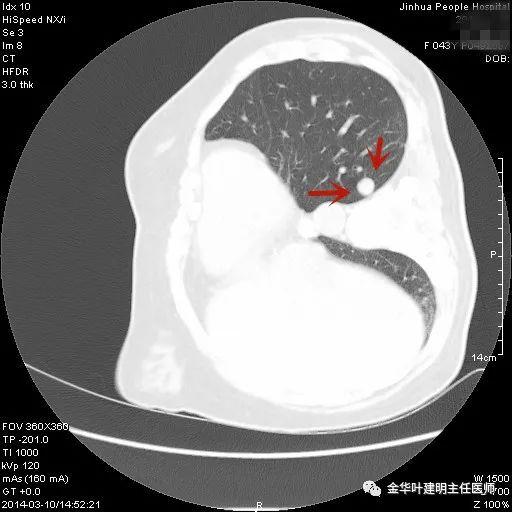

上图示隐球菌性结节。是典型的表现,高密度结节,周围部位,病灶有晕征,收缩力弱(邻近胸膜无牵拉凹陷)。